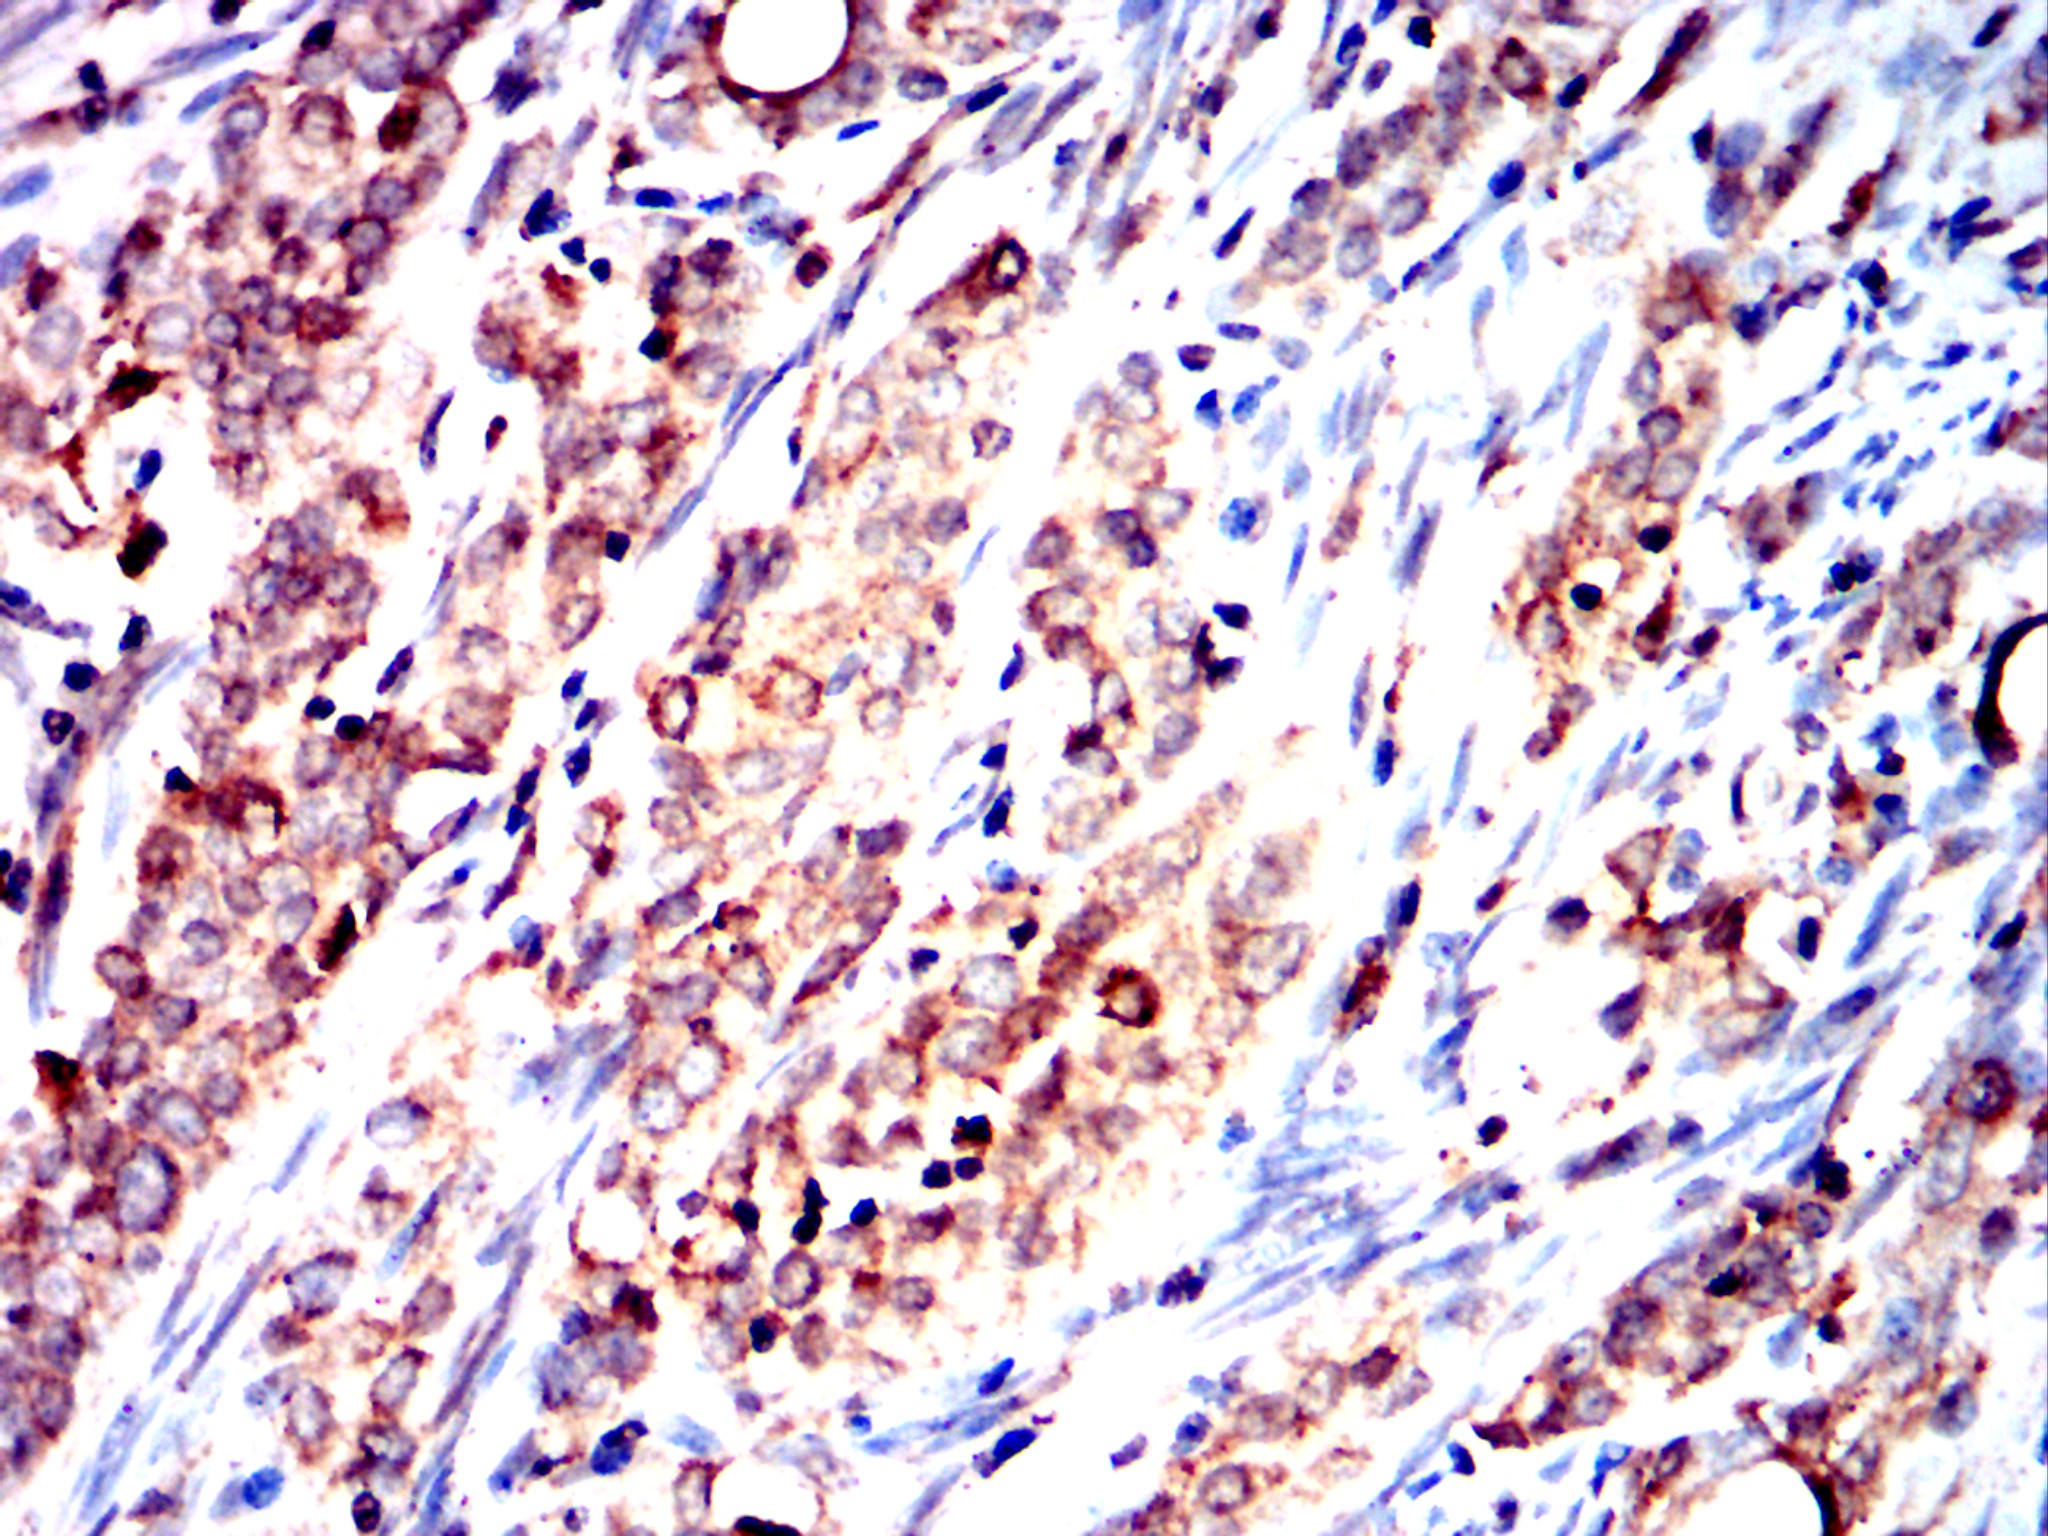

分类: 科研抗体货号: 32454别名: CEA;CD66e应用: IHC反应种属: Human